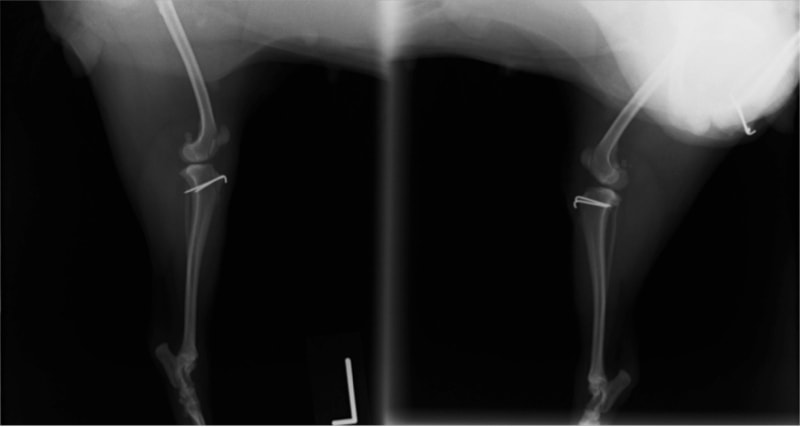

■ 症例24 キャバリア 7か月

左右膝蓋骨内方脱臼(左:グレードⅣ 右:グレードⅢ)

以前から左右後肢の跛行が認められ、整形外科学的検査・レントゲン検査により左右の膝蓋骨脱臼が認められた。症状が重度である左膝の膝蓋骨脱臼整復術を行った。外科手技は縫工筋及び内側広筋の解放、脛骨粗面の外側転位、滑車ブロック形造溝術、内外側関節方の縫縮を実施した。術後一か月時点で、左の膝蓋骨は安定しており経過は良好である。

本症例は成長期における重度の膝蓋骨脱臼であり、術後の再発の可能性もあるため、経過をしっかりと観察していく必要がある。また、今回手術を実施していない右膝に関しても経過を観察し、手術を検討していくこととする。